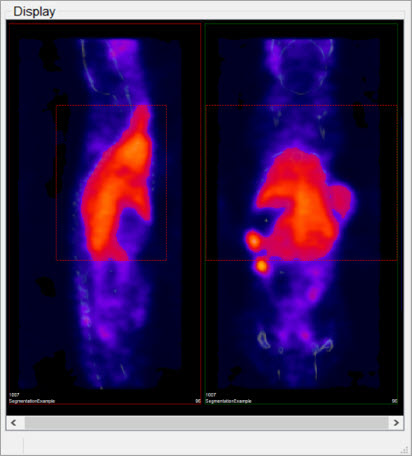

To perform any of the thresholding segmentation methods on only a sub-region of the input image, follow these steps:

-

Open the Cropping operator from the Operators drop-down menu.

Use the red sliders to select the desired region of the image.

- After you’ve selected the desired region, go back to the 3D ROI tool by selecting the 3D ROI operator from the Operators drop-down menu.

In the Expert tab of the 3D ROI Operator, mark the Crop Range checkbox. Dashed red lines will appear on the image, indicating the boundaries of the selected region.

- When the desired thresholding method is performed (see Segmentation Tools to learn how to use the Segmentation panel of the 3D ROI Operator), only the region within the crop range will be segmented.